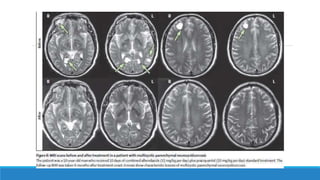

Neuroimagenes:

1. Radiografía simple del cráneo y partes blandas: pude demostrar las calcificaciones; signos

indirectos de hidrocefalia.

2. Tomografía Axial Computarizada (TAC): TAC de encéfalo con contraste , procedimiento

diagnóstico más útil revela formas activas, en degeneración e inactivas del cisticerco. Igualmente

NCC subaracnoidea con hidrocefalia, quistes intraventriculares. Encefalitis cisticercósica

(múltiples quistes), captadores de contraste en anillo (inflamación) y edema, con ventrículos

laterales pequeños.

3. Resonancia Magnética (RM): permite observar quistes no identificados por la TAC. Muestra

imágenes mejor definidas (escolex), quistes intraventriculares (III y IV) en distintos planos

espaciales. Su desventaja no detecta calcificaciones y su alto costo.